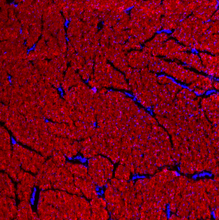

CHP is a powerful histopathology tool which enables straightforward detection of inflammation and tissue damage caused by a large variety of diseases, as well as tissue remodeling during development and aging. CHP robustly visualizes the pericellular matrix turnover caused by proteolytic migration of cancer cells within 3D collagen culture, without the use of synthetic fluorogenic matrices or genetically modified cells. CHP can measure and localize mechanical injury to collagenous tissue at the molecular level. It also enables assessment of collagen denaturation in decellularized extracellular matrix. In addition, CHP can be used to specifically visualize collagen bands in SDS-PAGE gels without the need for western blot.

- Cell invasion - reveal collagen turnover: Gain direct evidence of protease mechanisms by imaging degraded collagen in complex 3D settings. This robust method bypasses synthetic hydrogels and genetic modification, overcoming key assay limitations. Such clarity is vital for understanding cancer metastasis and finding new therapies against invasive diseases. More on cell invasion...

Histopathology - unlock new insights in tissue damage: CHPs precisely detect and quantify denatured collagen, a hallmark of disease. CHPs are applicable to nearly all tissue types and a wide range of medical areas. More on histopathology...